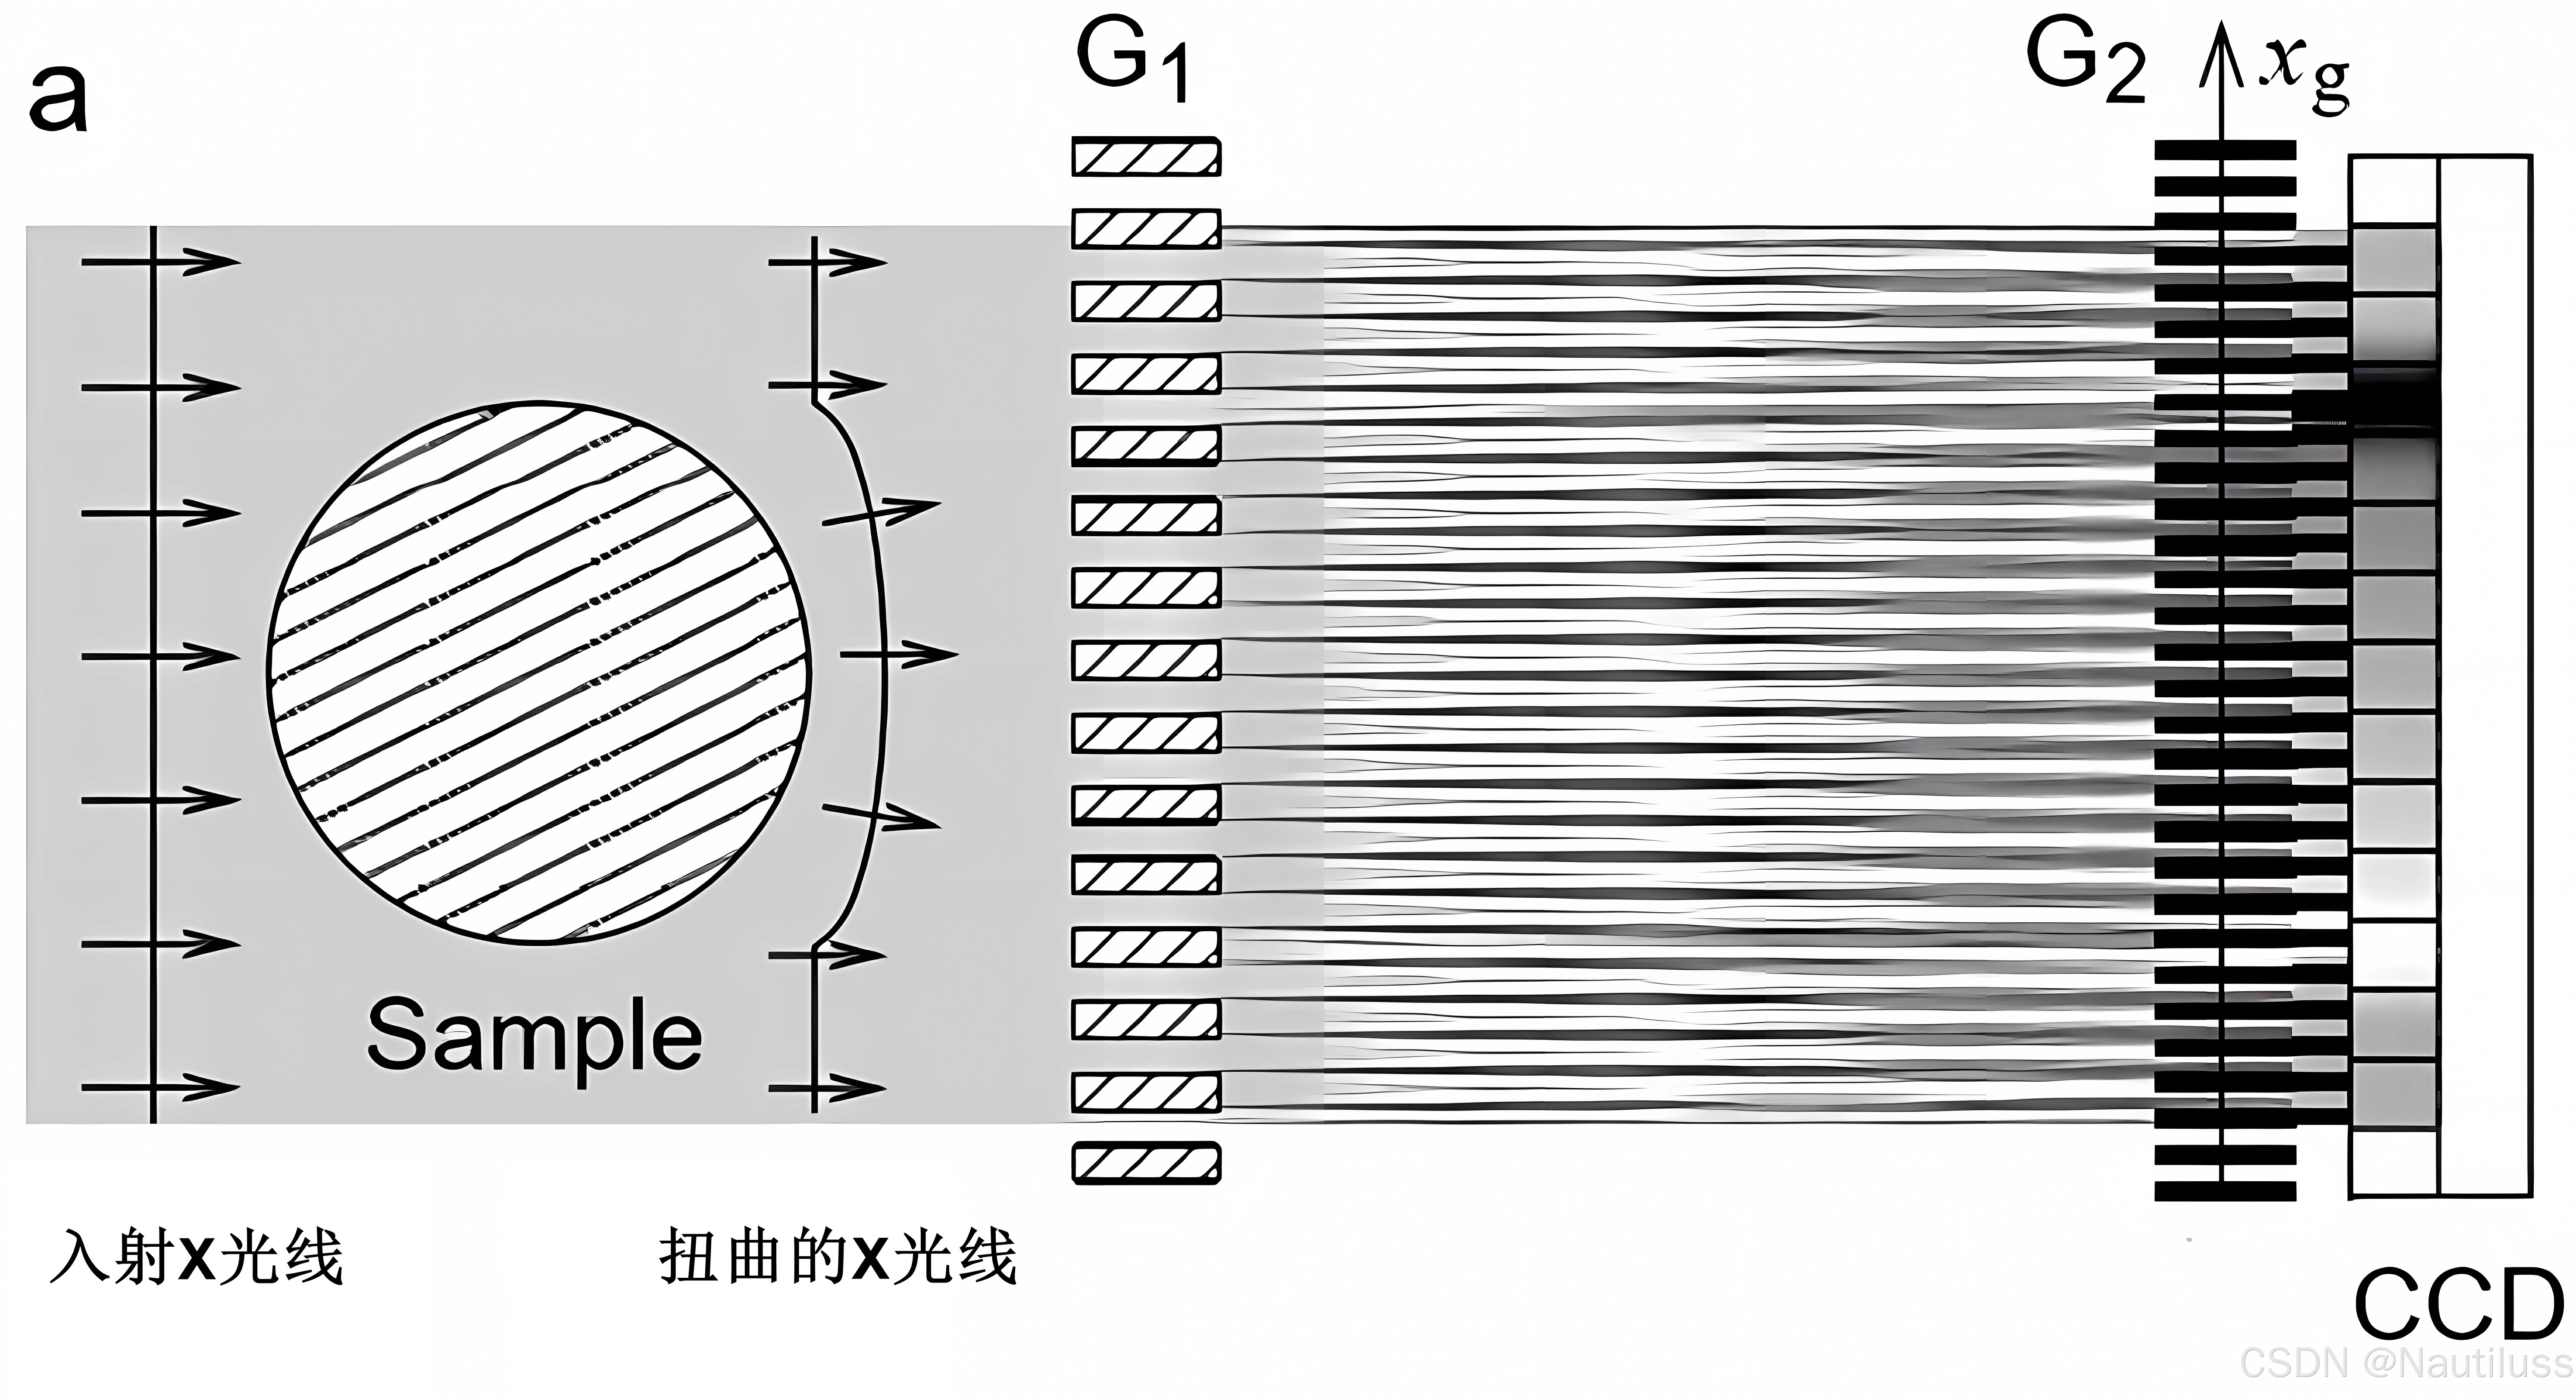

2、基于光栅的成像(GBI)

在光栅干涉仪中,第一个光栅 (G1 )将入射光束分成两个一级衍射。这两束光束在第一个光栅的下游衍射,相互干涉,并形成线性周期性条纹图案。相位物体的存在会引起条纹的位移。与条纹具有相同周期性和方向的第二个光栅(G2 )直接插入到探测器前面,以读取条纹并获得物体的折射。因此,可以从G2检测器上的步进读数恢复条纹。为了利用 G2将相位调制转换为强度调制,根据塔尔博特效应计算第一和第二光栅之间的距离。因此,这种方法也被称为“塔尔伯特干涉仪”。

然而,该方法还需要高度相干和高亮度的X射线源,限制了其在实验室源和商业用途中的应用。2006 年,Pfeiffer 等人。在该方法中引入了另一个光栅,因为该光栅紧邻 X 射线源放置。这个光栅创建了一系列单独相干但相互不相干的光源。由于 Lau 效应 ,这些光源的 Talbot 效应在 G2平面上相互重叠,使得该方法适用于非相干和低亮度光源。新引入的X射线光栅干涉仪也被称为“Talbot-Lau干涉仪”。使用 Talbot-Lau 干涉仪时,实验装置中的仪器校准相对简单,可实现大视场。该方法正在成为生物样品最流行的 X 射线相衬图像之一。